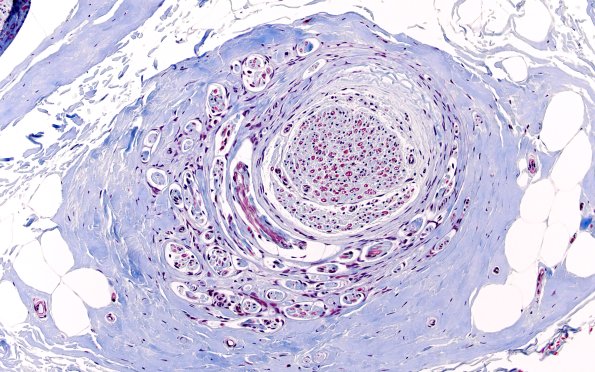

10E Neuroma (Case 10) TRI 20X

Mini-fascicles are surrounded by collagen. (Trichrome)